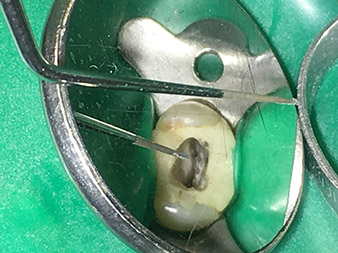

Dr Nouraie : J'aime tout particulièrement travailler avec l'insert 1E. Il est parfaitement adapté pour l'activation du liquide de rinçage dans le canal radiculaire. Grâce à sa conception délicate, l'insert vous permet d'atteindre même les parties les plus profondes du canal, pour une activation optimale.

Le renfort de matière prévu à la jonction entre l'embout et le corps de l'insert réduit les risques de cassure de cet instrument très fin.

Il est vraiment utile dans chaque traitement du canal radiculaire car il peut être utilisé pour l'activation du liquide de rinçage. On sait bien qu'avec la préparation le rinçage du canal radiculaire est l'étape la plus importante du traitement. Le liquide de rinçage activé pénètre plus profondément dans les tubules dentinaires, permettant d'obtenir de meilleurs résultats. Ainsi, l'activation du liquide de rinçage joue un rôle important dans l'amélioration de la qualité de ce type de traitement.